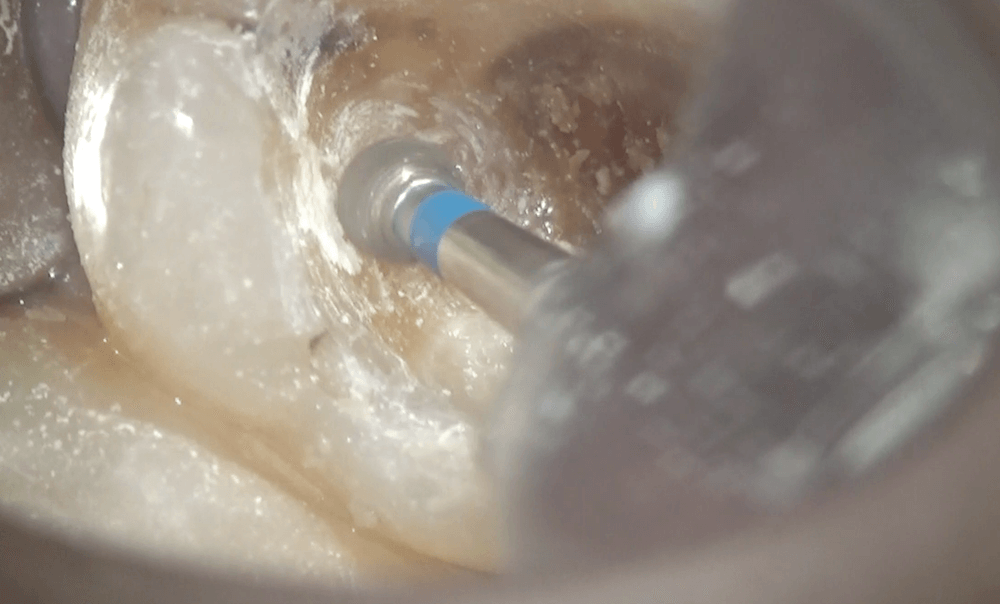

きれいになったところです。この上に

コンポジットレジンで土台を作り、本日は終了になります。